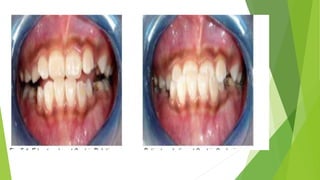

Indications:

1. Class I or mild Class III skeletal

discrepancy. If the patient can bite the

incisor teeth at

edge to edge in centric relation (pseudo-Class

III) [Fig. 5.1], the prognosis of treatment is

good.